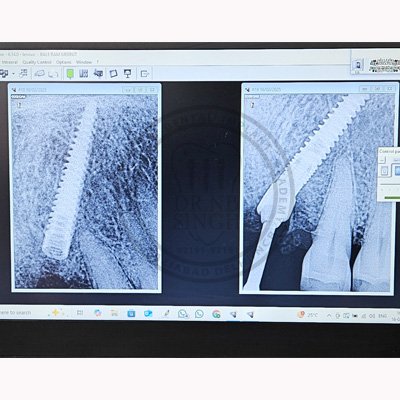

Case – 11 Baleram